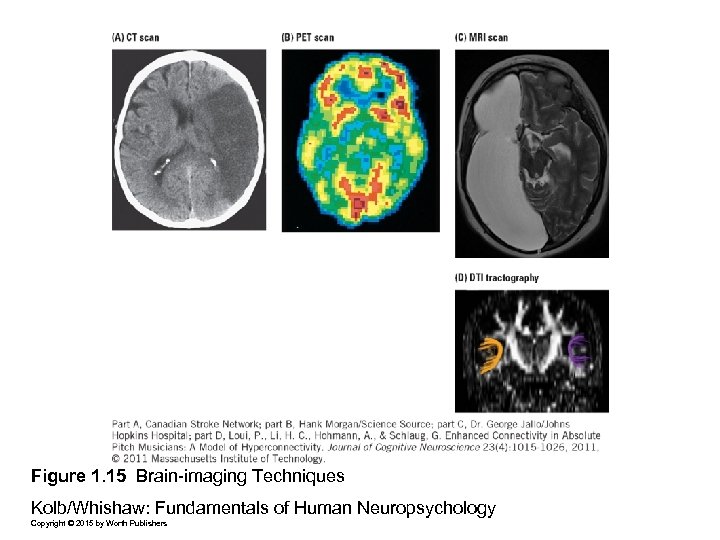

Figure 1. 15 Brain-imaging Techniques Kolb/Whishaw: Fundamentals of Human Neuropsychology Copyright © 2015 by Worth Publishers